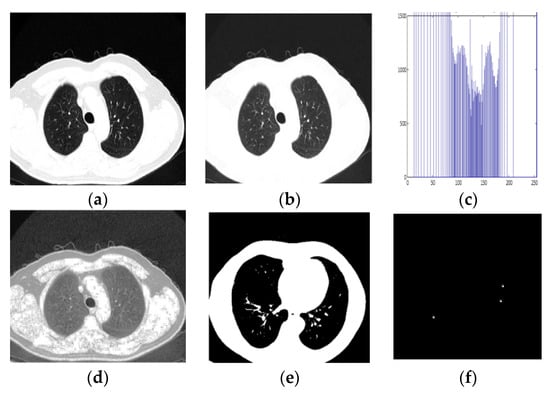

The Guaranteed Convergence Particle Swarm Optimization (GCPSO) algorithm is based on a new Particle Swarm Optimization (PSO) algorithm-based optimisation solution, which considers that each particle is evaluated according to the suitable location in the current region [16,35]. GCPSO was applied for segmentation purposes. At this point, the parameters for the “NC” and “MC” thresholds were defined empirically. During some iterations, gaining a better value in high-dimension search space is difficult. So, the values that are being suggested are “NC” = 15 and “MC” = 5, respectively. For the GCPSO, different phases are included to improve the solution process. In some comparative studies, the GCPSO has demonstrated remarkable progress in searching within a minimum space with only a small number of particles [36]. In this sense, GCPSO was used to enhance the research segmentation results. Figure 6 represents the algorithm steps and the obtained images after implementation using the GCPSO, given in Algorithm 1.

Figure 6.

Segmentation results after applying the GCPSO algorithm.

The step-by-step segmented output and classification procedure for the proposed method is shown in Figure 9 and Figure 10 (for the benign and malignant dataset). It is an image-calculated tumor area based on the nano technique, and the status of the tumor area of the malignant sample is shown in Table 5.

Figure 9.

Detection of Benign Sample. (a) Input CT Image, (b) Pre-processed output, (c) Histogram Equalised Image Plot, (d) Histogram Equalised Image, (e,f) Segmentation image, (g) Classification result.